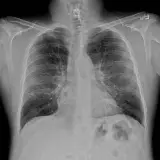

Over 2,100 interactive radiology cases, curated by radiologists for your level of training. Scroll, window, and view cases full screen — just like on PACS. Click linked findings in each writeup to jump straight to them on the image. Cases include sample reports, a focused discussion section, original illustrations, and videos.

PACSで期待されるツールを完備した完全インタラクティブな症例 — スクロール、ウィンドウ調整、ズーム、パン、計測、ROI、フルスクリーンモード。

重要な所見を症例画像上に直接ハイライトする豊富なアノテーション。症例解説内のリンクされた所見をクリックすると、スキャン上の正確な位置へジャンプできます。